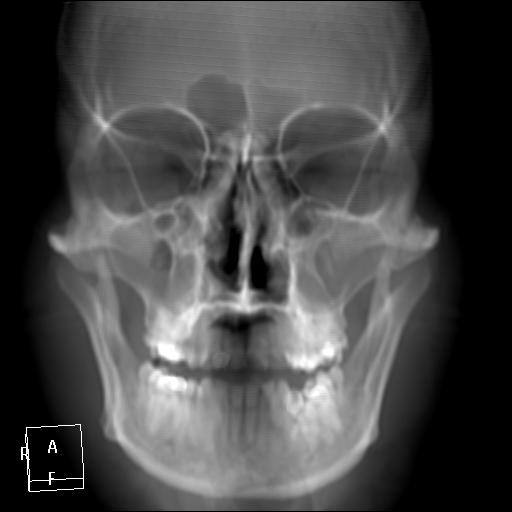

КТ ППН и носоглотки. Девушка 21 года. Полипозный риносинусит.

Госпитализирована для оперативного лечения. Удалены полипы носа. Вторым этапом планируется гайморотомия. Во время операции - подозрение на образование носоглотки. Сохраняется затруднение носового дыхания. Направлена на КТ. Категорически отказалась от контрастировния (лекарственная полиаллергия, боится).

Полип в носоглотке справа. Нарушена пневматизация придаточных пазух носа кроме левой решётчатой. В левой гайморовой на дне неясно что…

На дне гайморовой - полип, в носоглотке немаленький хоанальный полип. Там всё в полипах, а они и фиброзные бывают, и ангиофибромы, и ангиоаденомы... Вот и плотность разная.

Ну, как-то все в одну кучу - и полипы, и ангиофибромы. При ангиофиброме, например, околоносовые пазухи свободны. А гиперденсность более характерна для грибкового поражения (аспергилеза), в том числе и "севшим" на пломбировочный материал.

На операции визуально полипы аденоматозного типа. Какие будут гистологически после гайморотомии - сейчас трудно сказать. Если б гиперденсность была только по нижней стенке верхнечелюстной пазухи, тогда вариант с аспергиллезом на пломбировочном материале, на мой взгляд, был бы более вероятен. У девушки участки гиперденсности по всем стенкам верхнечелюстных пазух, в основной пазухе, совсем чуть - в решетчатом лабиринте слева, без костной деструкции. Без посева и гистологии - только гадать)). В носовой полости признаков грибкового поражения ЛОРы не отмечают. Но Вы правы, может иметь место изолированное поражение синусов.